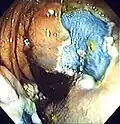

-

Polyp is identified. -

A sterile solution is injected under the polyp to lift it away from deeper tissues. -

A portion of the polyp is now removed. -

The polyp is fully removed.